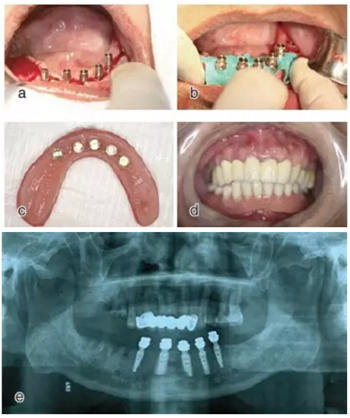

種植后修復(fù)

戴上套筒冠基臺進行即刻修復(fù)。注意不是所有植入的種植體都可以進行即刻修復(fù),醫(yī)師可以通過扭力值并結(jié)合ISQ松動度測量值來選擇修復(fù)的種植體。

圖18 進行即刻修復(fù):a.戴上基臺;b.在基臺上戴入套筒冠;c. 套筒冠固位到原有義齒上;d.患者戴上有套筒冠的覆蓋義齒;e. 即刻修復(fù)完成后曲面體層片